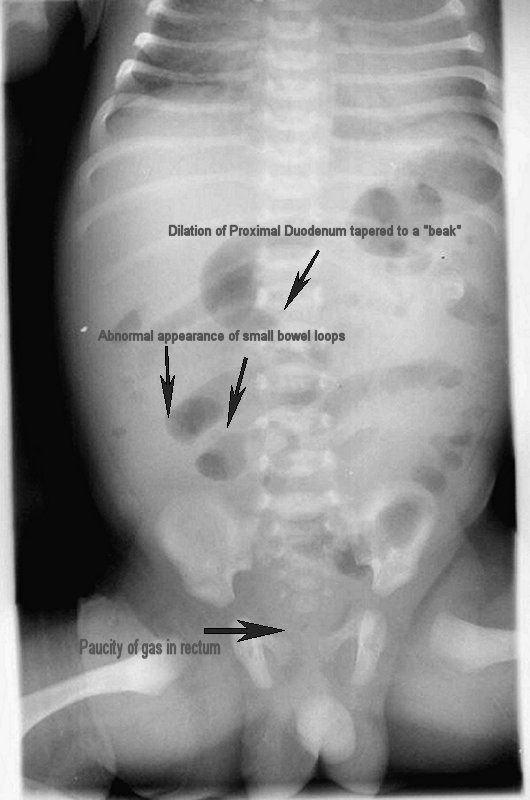

Midgut volvulus “small intestinal beak” sign